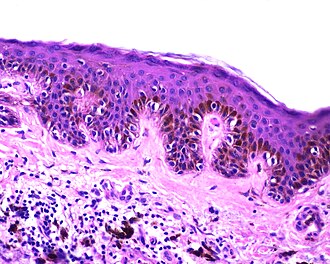

Template:Px Simple lentigo. H&E stain. (WC) | |

| LM | melanocytes in epidermis only - hyperpigmentation; no melanocytic nests; +/-mild/moderate elongation of the rete ridges |

- Melanocytes in epidermis only.

- Melanocytes basally located (normal location) with hyperpigmentation.

- No melanocytic nests.

- +/-Mild/moderate elongation of the rete ridges.[6]

The sections show skin with increased numbers of small pigmented melanocytes at the dermal-epidermal junction. The rete ridges are mildly elongated. No solar damage is apparent. No dermal melanocytes are identified. No melanocytic nests are identified. No nuclear atypia is apparent.